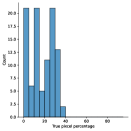

A few sample images and the corresponding masks of the polyp dataset in HyperKvasir are shown in Fig 2. The polyp images are RGB images. The masks of the polyp images are single-channel images with white () for true pixels, which represent polyp regions, and black () for false pixels, which represent clean colon or background regions. In this dataset, there are different sizes of polyps. The distribution of polyp sizes as a percentage of the full image size is presented in the histogram plot in Fig 3, and we can observe that there are more relatively small polyps compared to larger polyps. Additionally, a subset of this dataset was used to prove that the performance of segmentation models trained with small datasets can be improved using our SinGAN-Seg pipeline, and the whole dataset was used to show the effect of using SinGAN-Seg generated synthetic images instead of a large dataset which has enough data to train segmentation models. In this regard, this dataset was used for two purposes:

To understand the difference between the mask distribution of real images and synthetic images, we plotted pixel distribution of masks of synthetic images in Fig 6. This plot is comparable to the pixel distribution presented in Fig 3. The randomness of the generations made differences in the distribution of true pixel percentages compared to the true pixel distribution of real masks of real images. However, the overall shape of synthetic data mask distribution shows a more or less similar distribution pattern to the real true pixel percentage distribution.